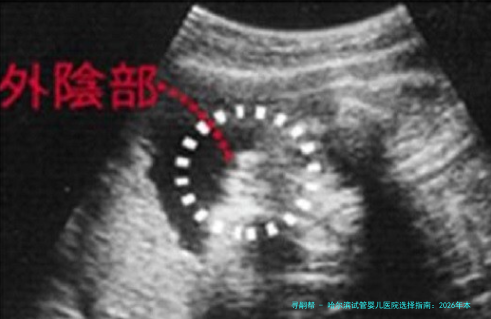

问:试管婴儿能选择生男生女吗? 答:在我国,除非患有特定的伴性遗传疾病(即疾病传男不传女或传女不男),经过严格的伦理委员会审批,才可以通过第三代试管婴儿技术(PGD/PGS)进行胚胎性别筛选,以防止遗传性疾病传送。简单出于个人喜好是法律明令禁止的。